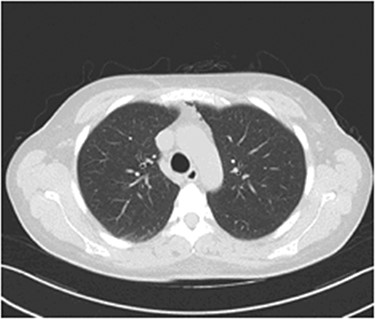

The possibility of pulmonary embolism was put first on the differential diagnosis list. In order to exclude this life-threatening complication, D-dimers and computed angiography of the pulmonary arteries were performed. Computed Tomography of the Pulmonary Arteries (CTPA) (Fig. 1) showed normal contrast enhancement of the pulmonary arteries, with no contrast deficits. Nevertheless, it brought out the presence of gas inside the mediastinum (capnomediastinum). Consequently, the D-dimers came out negative.

CTPA images show the presence of gas in the upper anterior mediastinum.